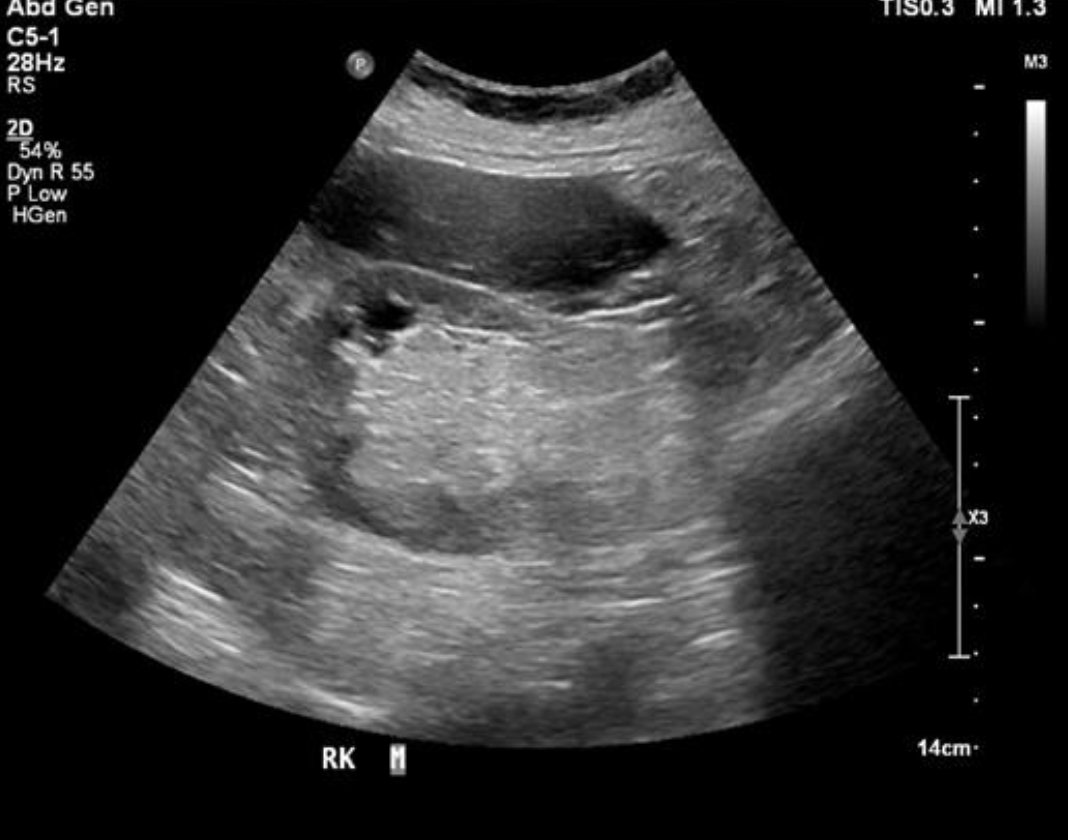

RCC (Renal Cell Carcinoma) → most common primary malignant tumor of the kidney

clinical hx: male, late middle age, smoking, ACDK, von Hippel Lindau, Tuberous sclerosis

s/sx: microscopic hematuria

2D US: solid, usually isoechoic but can vary, renal vein and IVC involvement, typically solitary and invades into surrounding vasculature

color doppler: vascular

DDX: AML, TCC